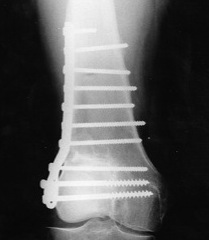

Currettage / Bone graft / Fixation

Resection and arthroplasty

Indications

Articular cartilage not salvageable